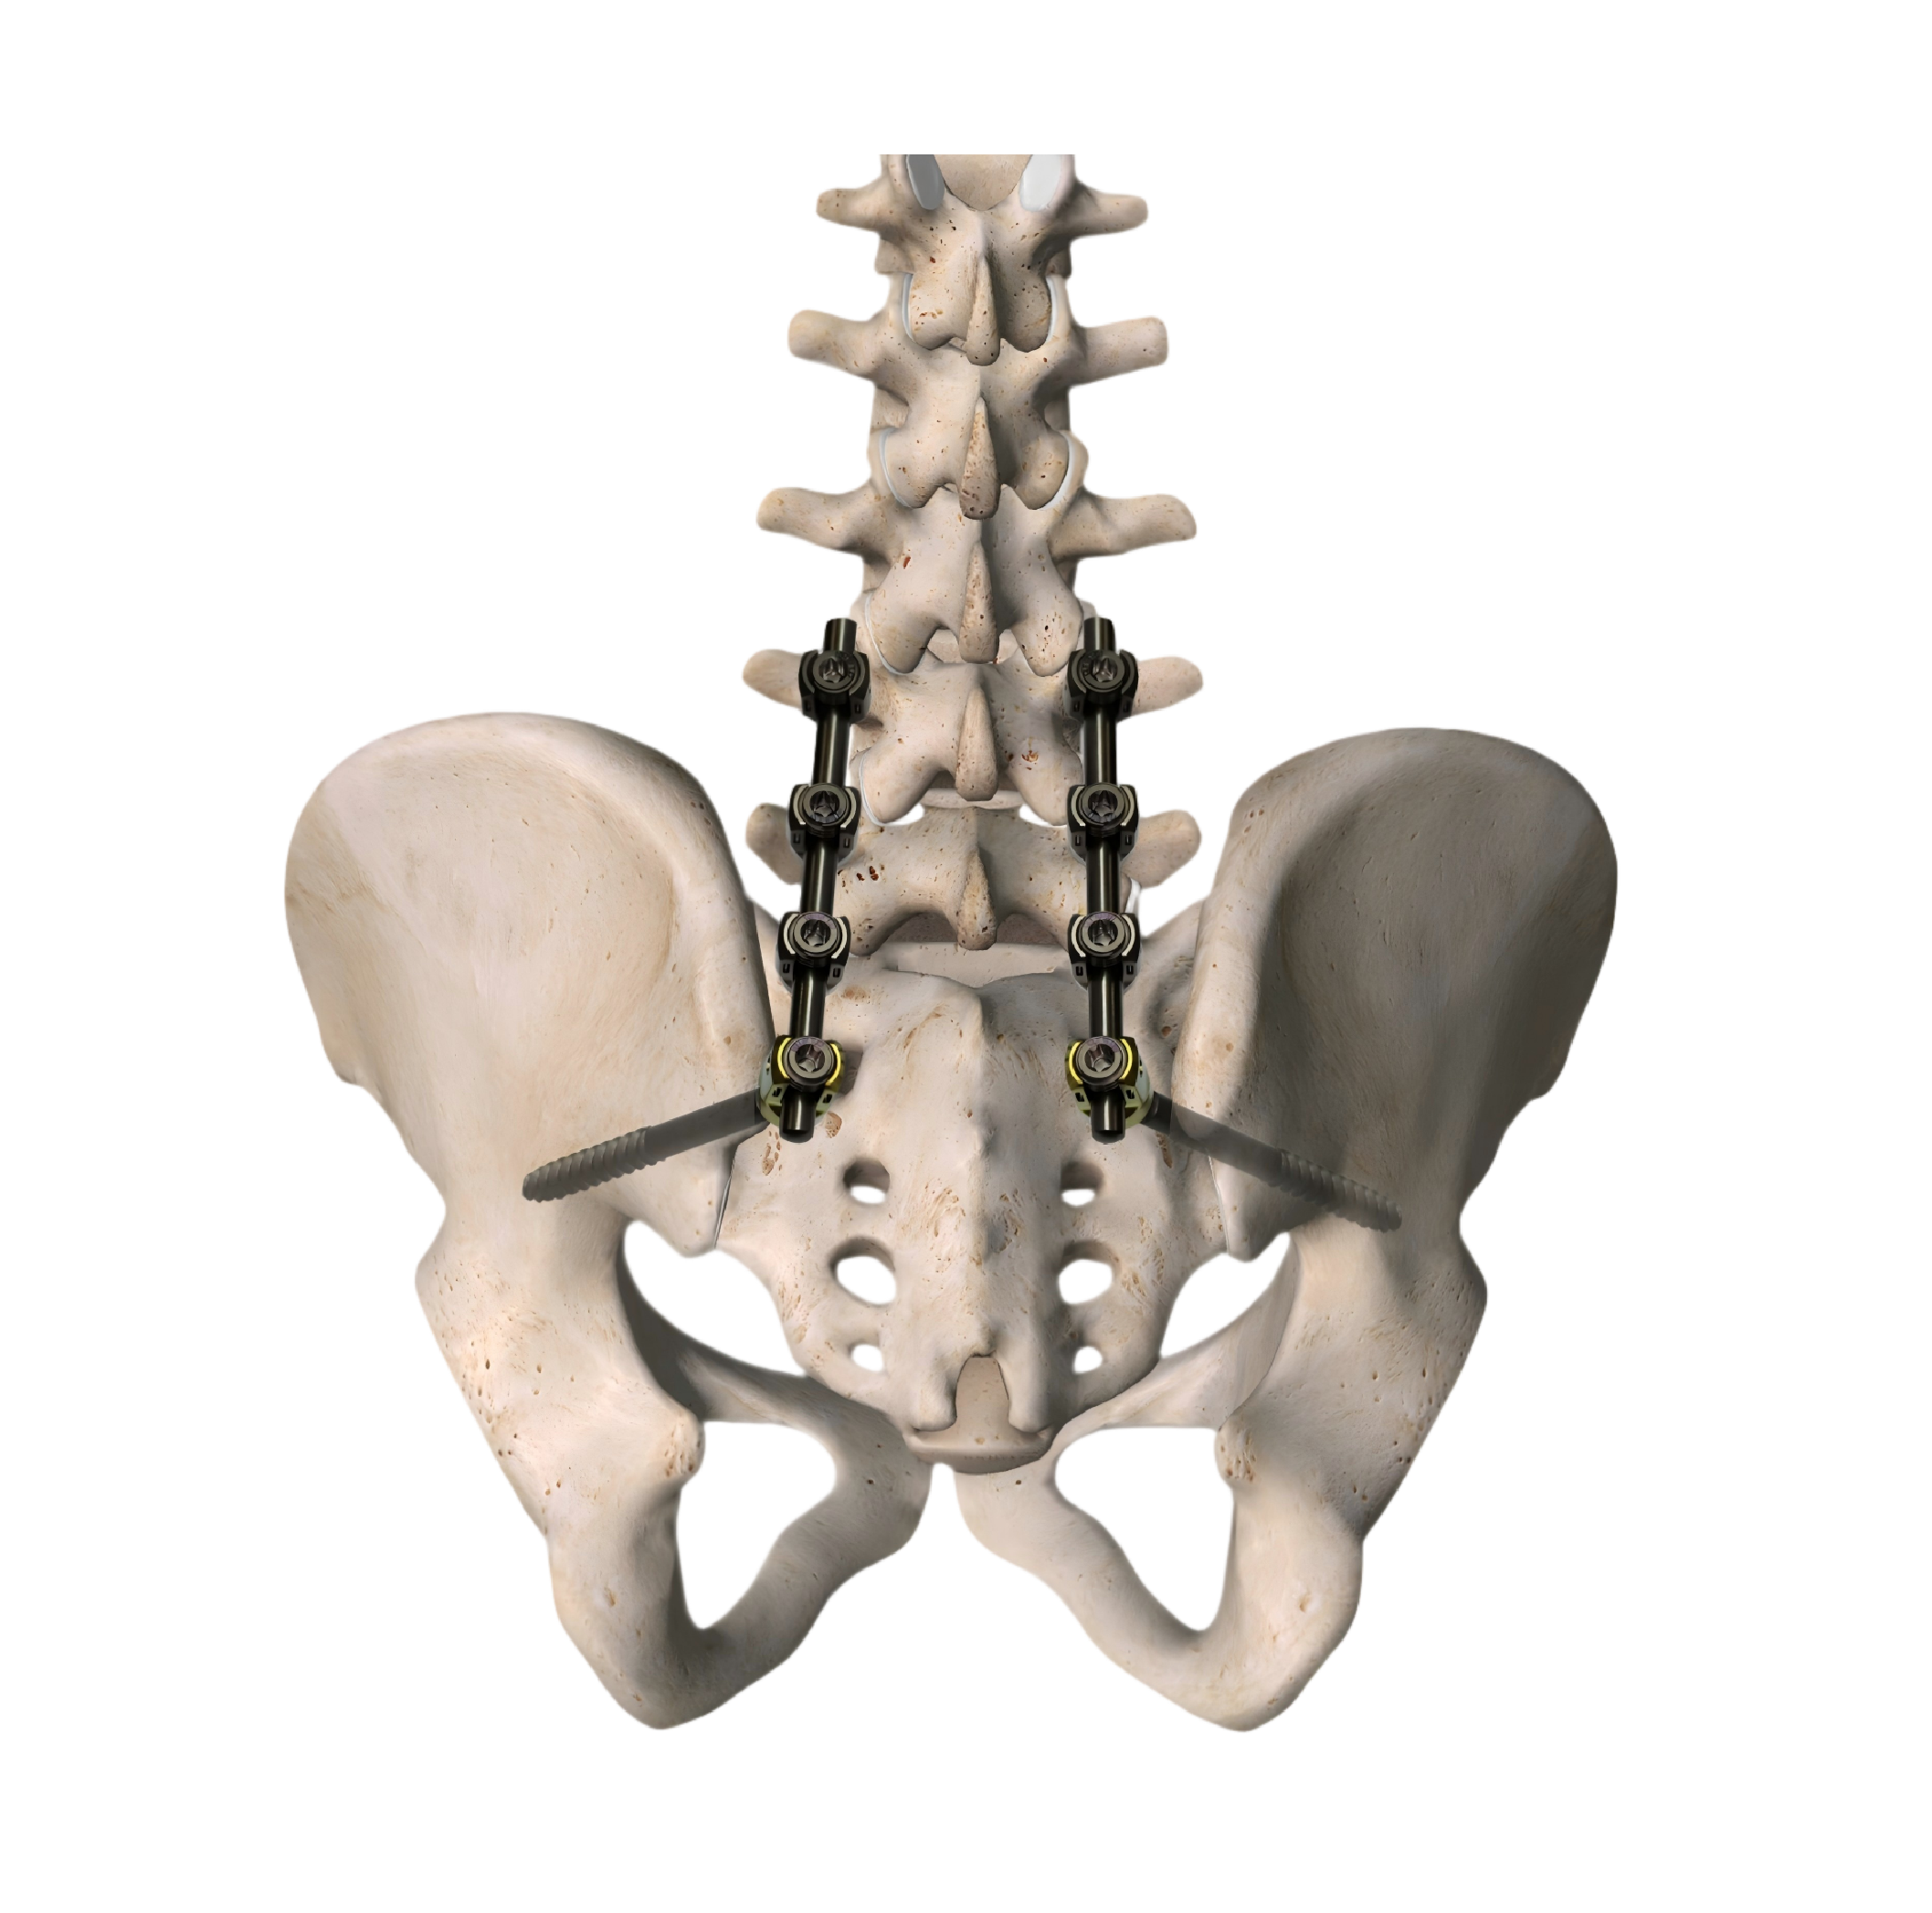

Spinal products

Spinal Internal Fixation System (Iliac)